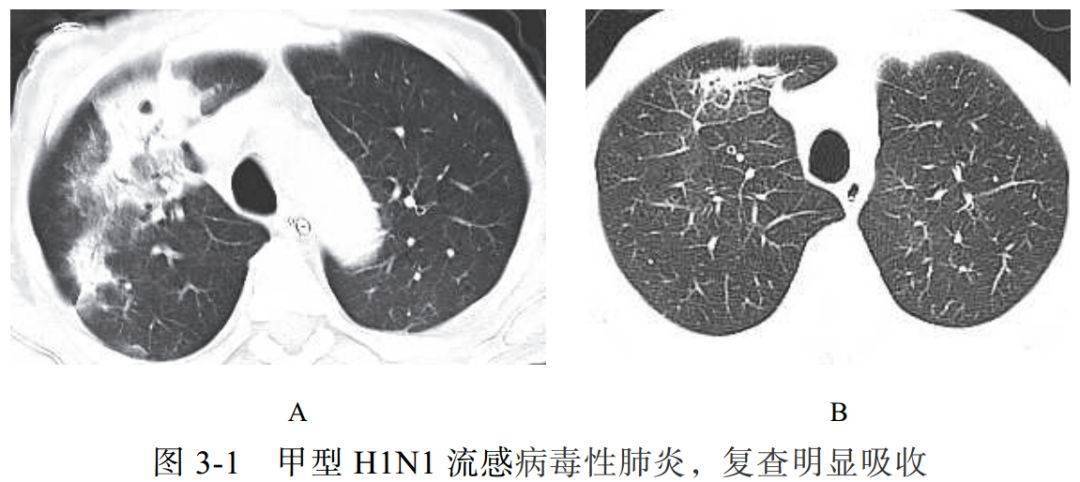

(一)流感病毒性肺炎

流感病毒属于正黏液病毒科的病毒种类,均为单链 RNA 病毒,并根据其内膜系统和核蛋白抗体分为三型(甲型、乙型、丙型),以甲型导致的流感病毒性肺炎常见,如 H1N1、 H5N1、 H7N9 等

疾病的早期常表现为气管支气管炎和支气管肺炎,气道壁充血,可见单核细胞肿胀和上皮细胞变性

晚期实质改变表现为弥漫性肺泡损伤的典型特征,肺泡内水肿、出血

影像学表现:

(1)早期从一侧叶开始,进展期双肺逐渐进展,磨玻璃样、斑片状实变影快速融合(代表弥漫性肺泡损伤或双重感染)

(2)恢复期病变吸收变淡,出现条索状影、网格影(图 3-1A),背景小叶间隔增厚,以及出现肺气囊、肺气肿

(3)最早出现的病灶则最晚吸收

(4)一般于 3 周内吸收、纤维化(图 3-1B)